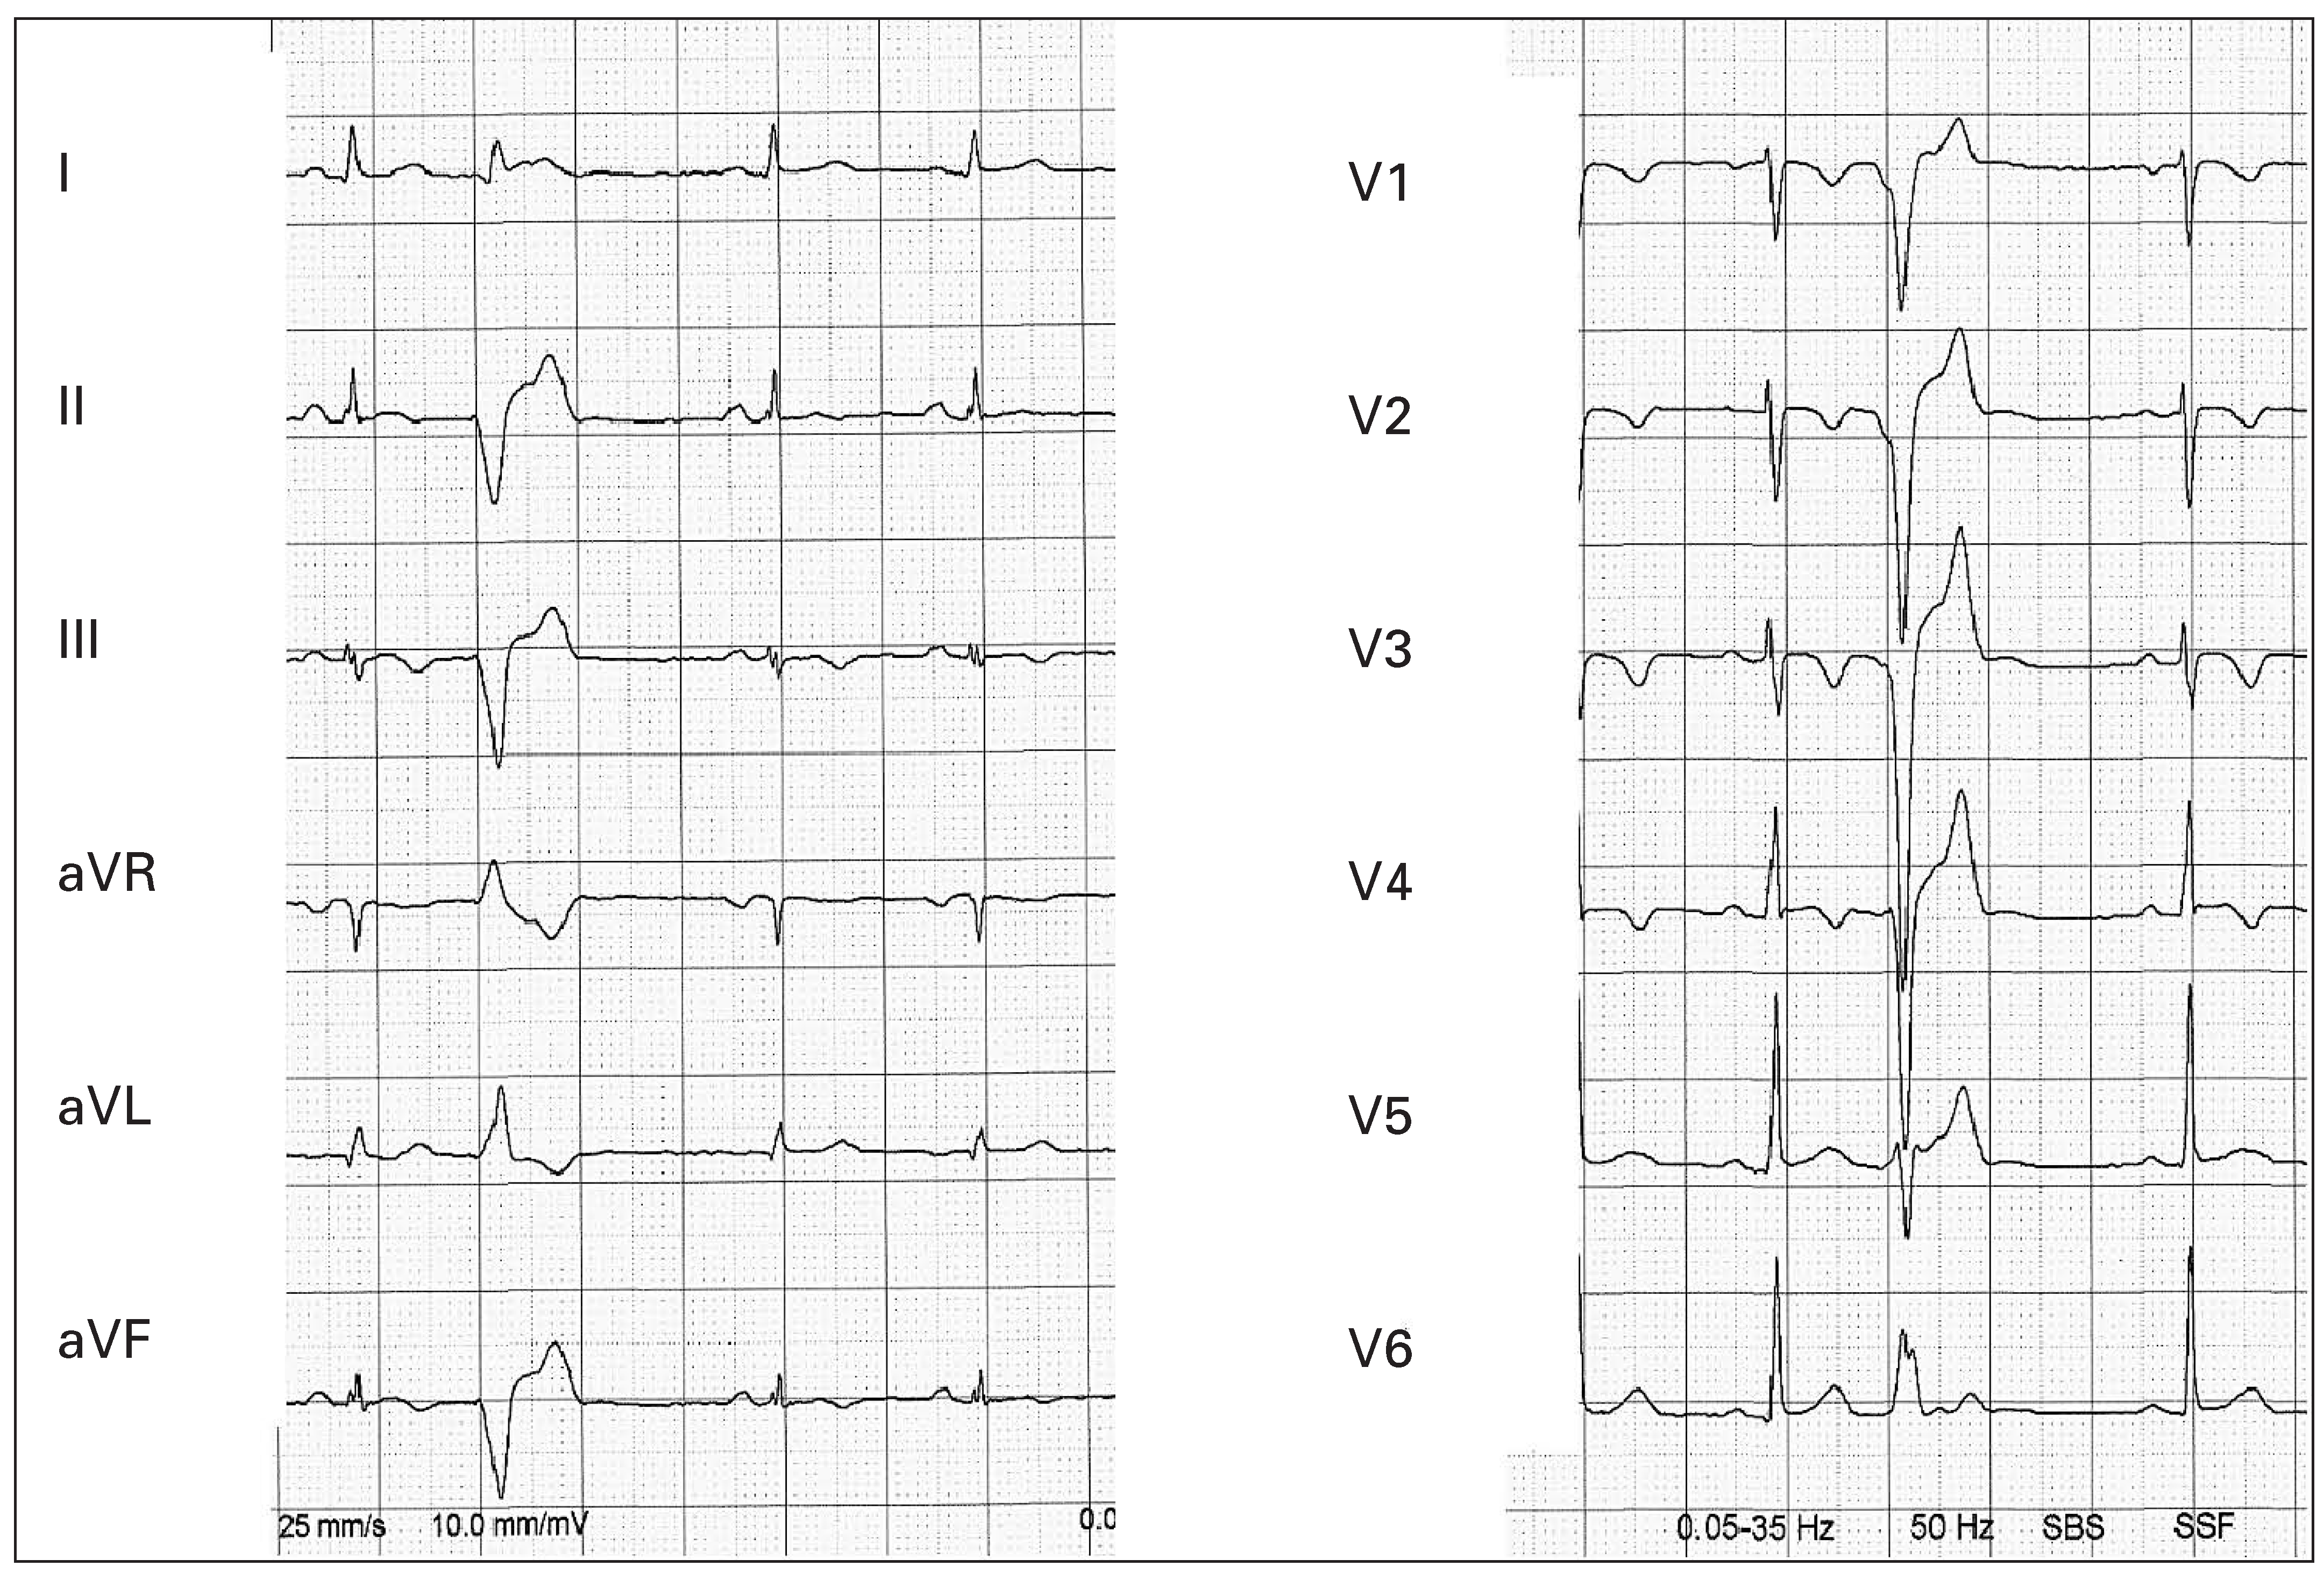

Ursprung der Extrasystolen

Fallbeschreibung

Diskussion